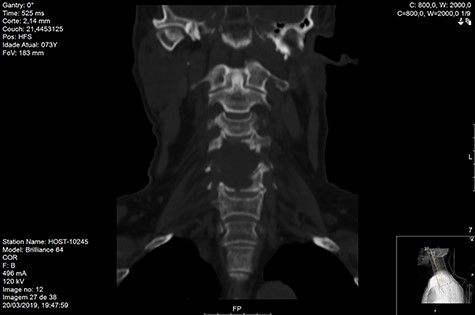

Computed tomography (CT) (Figs 1–3) and magnetic resonance imaging (MRI) (Figs 4–6) of the cervical spine were performed and revealed a lytic lesion involving most of C4, C5 and C6 vertebral bodies with bilateral extension to the posterior spinal elements of C4 and C5 and complete disruption of C4-C5 and C5-C6 intervertebral discs.

The Spinal Instability Neoplastic Score (SINS) [4, 6, 7] for assessing spinal instability from metastatic disease was used and the lesion was deemed unstable (SINS 13), with impending risk of increased neurological damage.